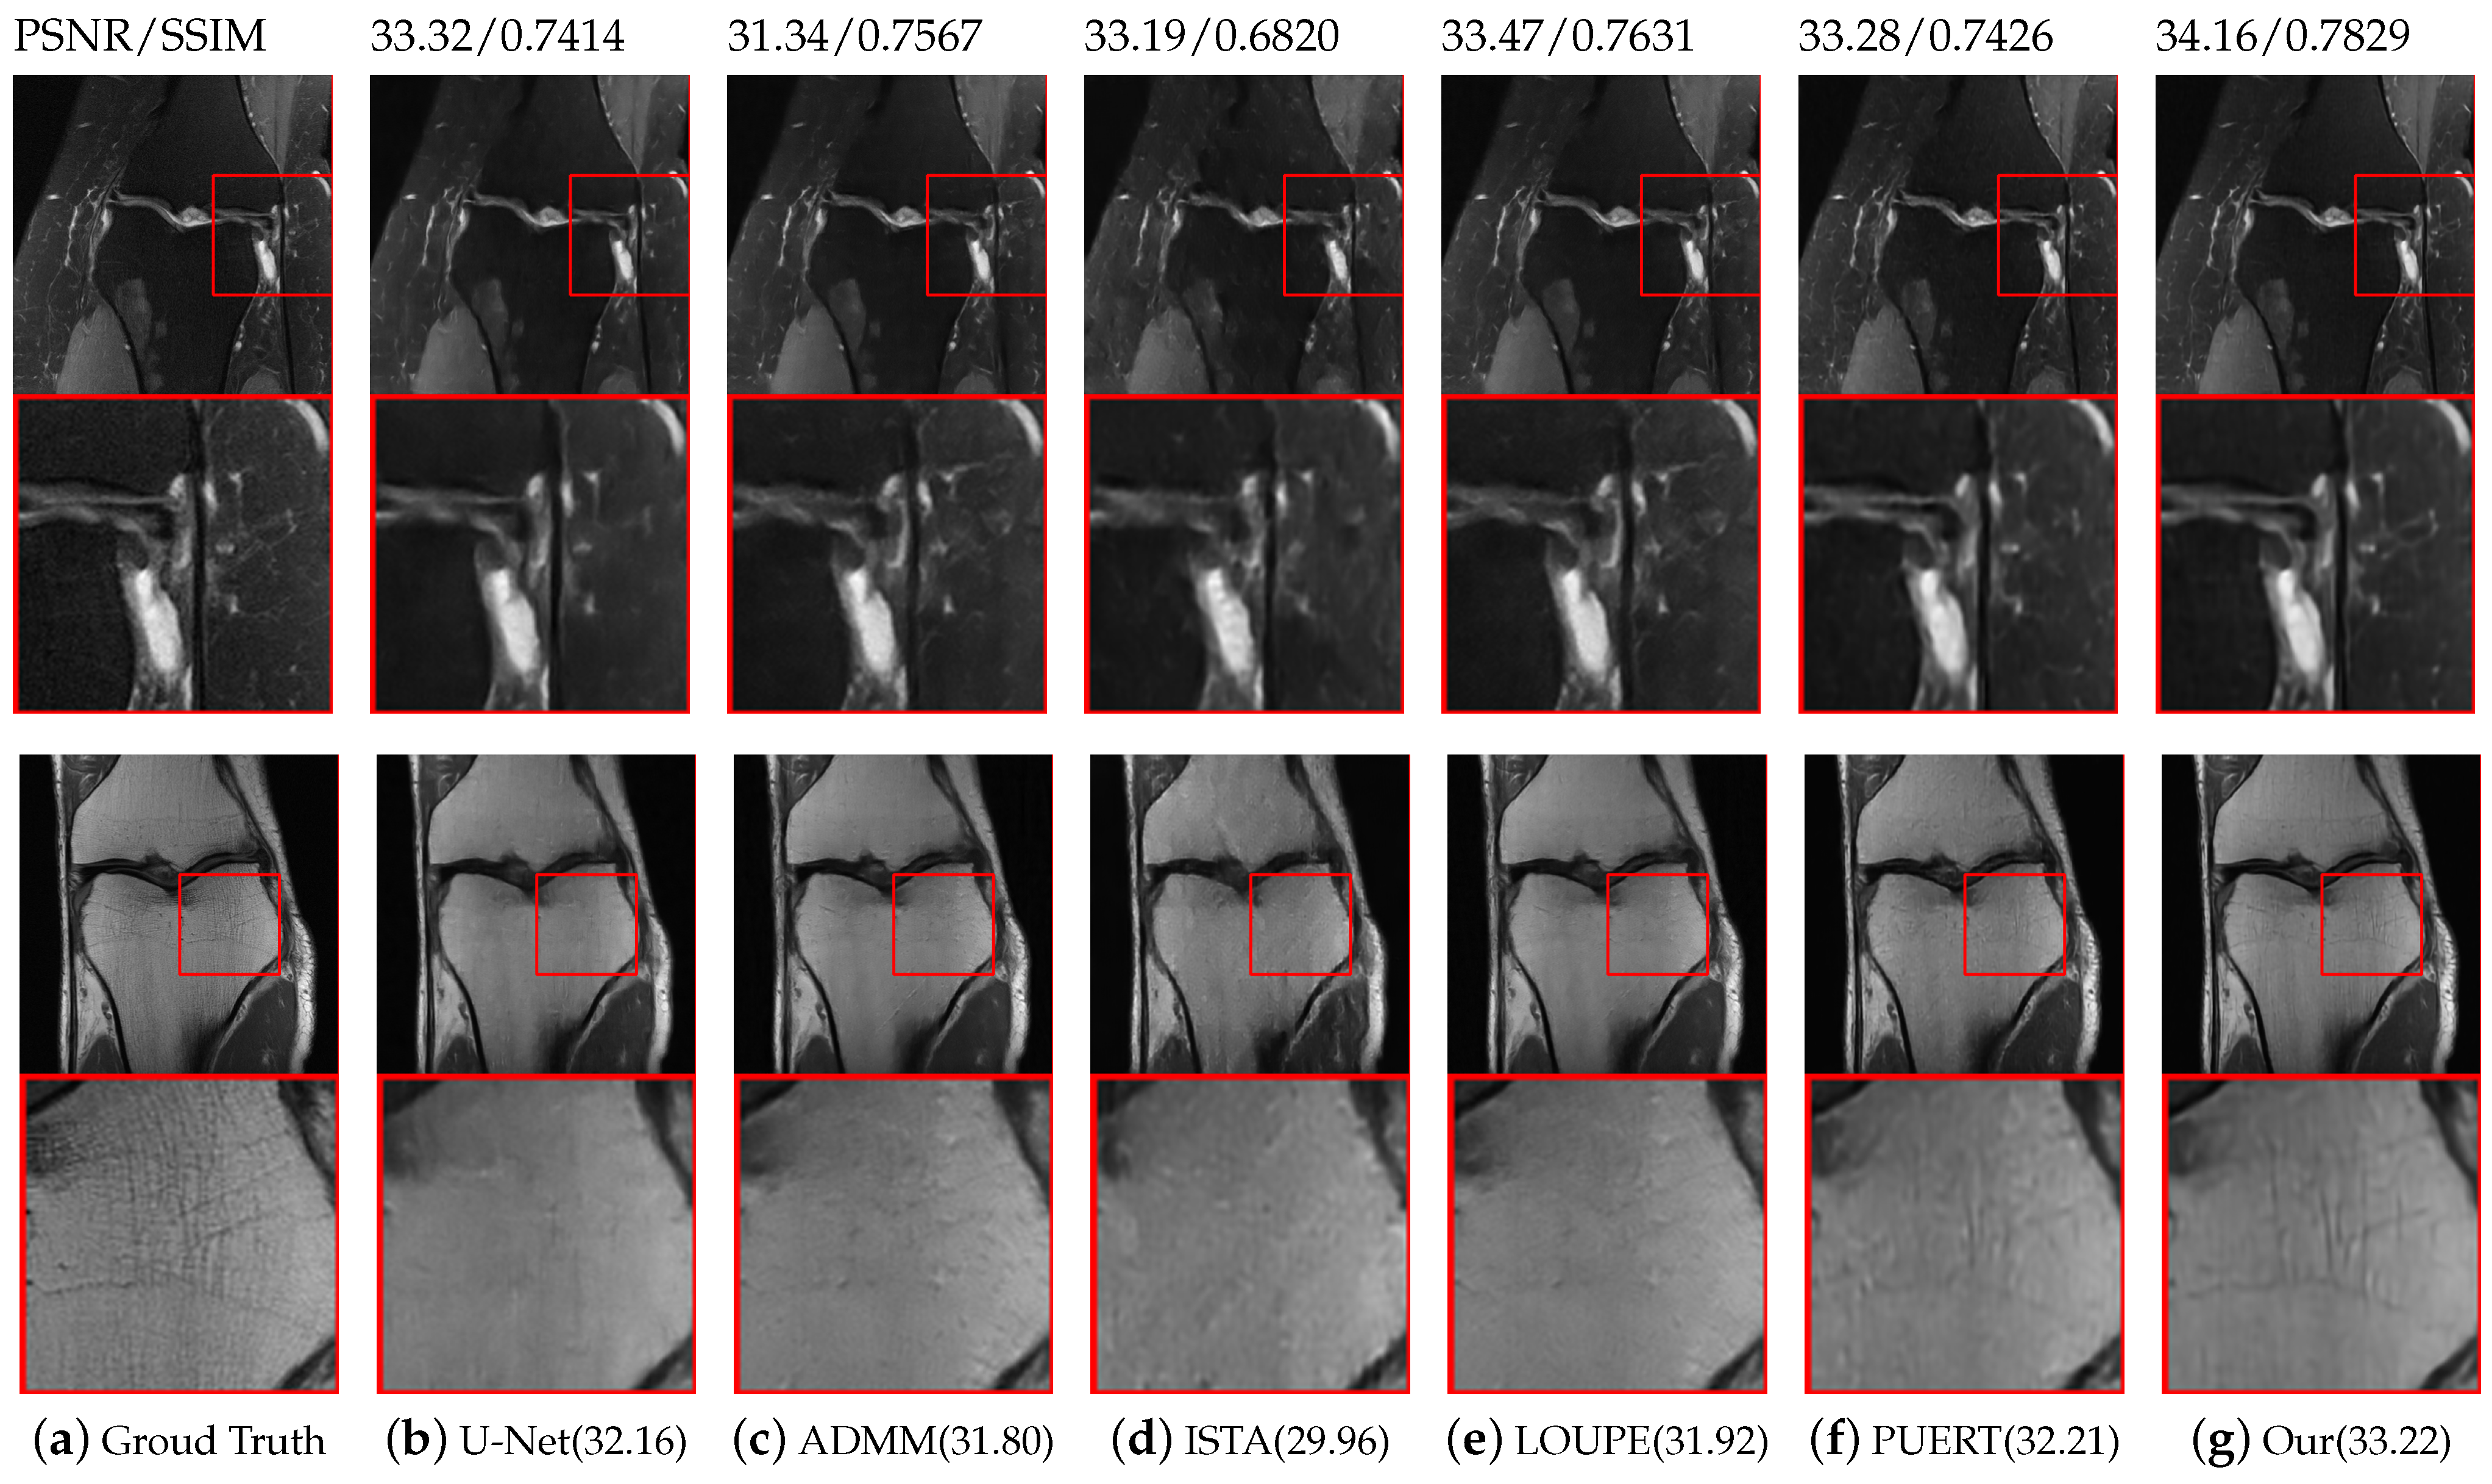

We compare the proposed reconstruction model with five representative state-of-the-art methods, namely U-Net [17], ADMM-Net [29], ISTA-Net [15], PUERT [22], and LOUPE [34]. The first three methods are reconstructed networks trained under a certain fixed sampling mask, while the latter two methods jointly optimize the learnable sampling mask and reconstruction network parameters. When performing comparative experiments, we used radial masks on the Brain and FastMRI datasets for tasks trained under fixed masks. Three learnable sampling masks enable both 1 D and 2 D sub-sampling optimization. Table 2 summarize the average PSNR/SSIM performance reconstruction at three CS ratios by various methods on the two datasets. It can be observed from the table that methods that use learnable sampling patterns generally produce higher PSNR than those with fixed masks, which confirms the superiority of the learned sampling mode.

Specifically, compared with the probability-based sampling mode optimization scheme employed by LOUPE and PUERT, it can be seen that at a sampling ratio of 5 % , the PSNR and SSIM of our model are significantly improved on both the Fast-MRI and Brain datasets. This is due to the fact that the data structure learned by our sampling mask is more pronounced at low sampling rates. On the Brain dataset, the gap between the proposed model and the results produced by PUERT   2 D and LOUPE   2 D narrows as the sampling ratio increases, which also shows that as previously mentioned, a 20 % sampling ratio can restore good results. On the Knee dataset, under three different sampling ratios, the proposed model performs slightly better than PUERT and LOUPE. In particular, at a sampling ratio of 5 % , the PSNR obtained is significantly increased by 0.77 compared with the PUERT results. This is because, with the large dataset, the sampling ratio is 20 % is still not enough for the Knee dataset. Under these circumstances, prior knowledge of the data structure is particularly important, while the masks we learn can help the reconstruction task. It can be observed from Table 2 that the use of neural networks enable five representative state-of-the-art methods to achieve real-time reconstruction speeds. As is shown in Figure 8, with a CS ratio of 10 % , the proposed model produces more reliable and clearer visual reconstructions than the other models in the comparison. In conclusion, the two experiments using two widely used MRI datasets indicate that the proposed model is superior to state-of-the-art methods in both quantitative indicators and visual quality.

Figure 8. Visual reconstruction comparisons with various state-of-the-art methods on the FastMRI [43] dataset with a CS ratio of 10%. Our model can recover more realistic details without producing overly smooth results.